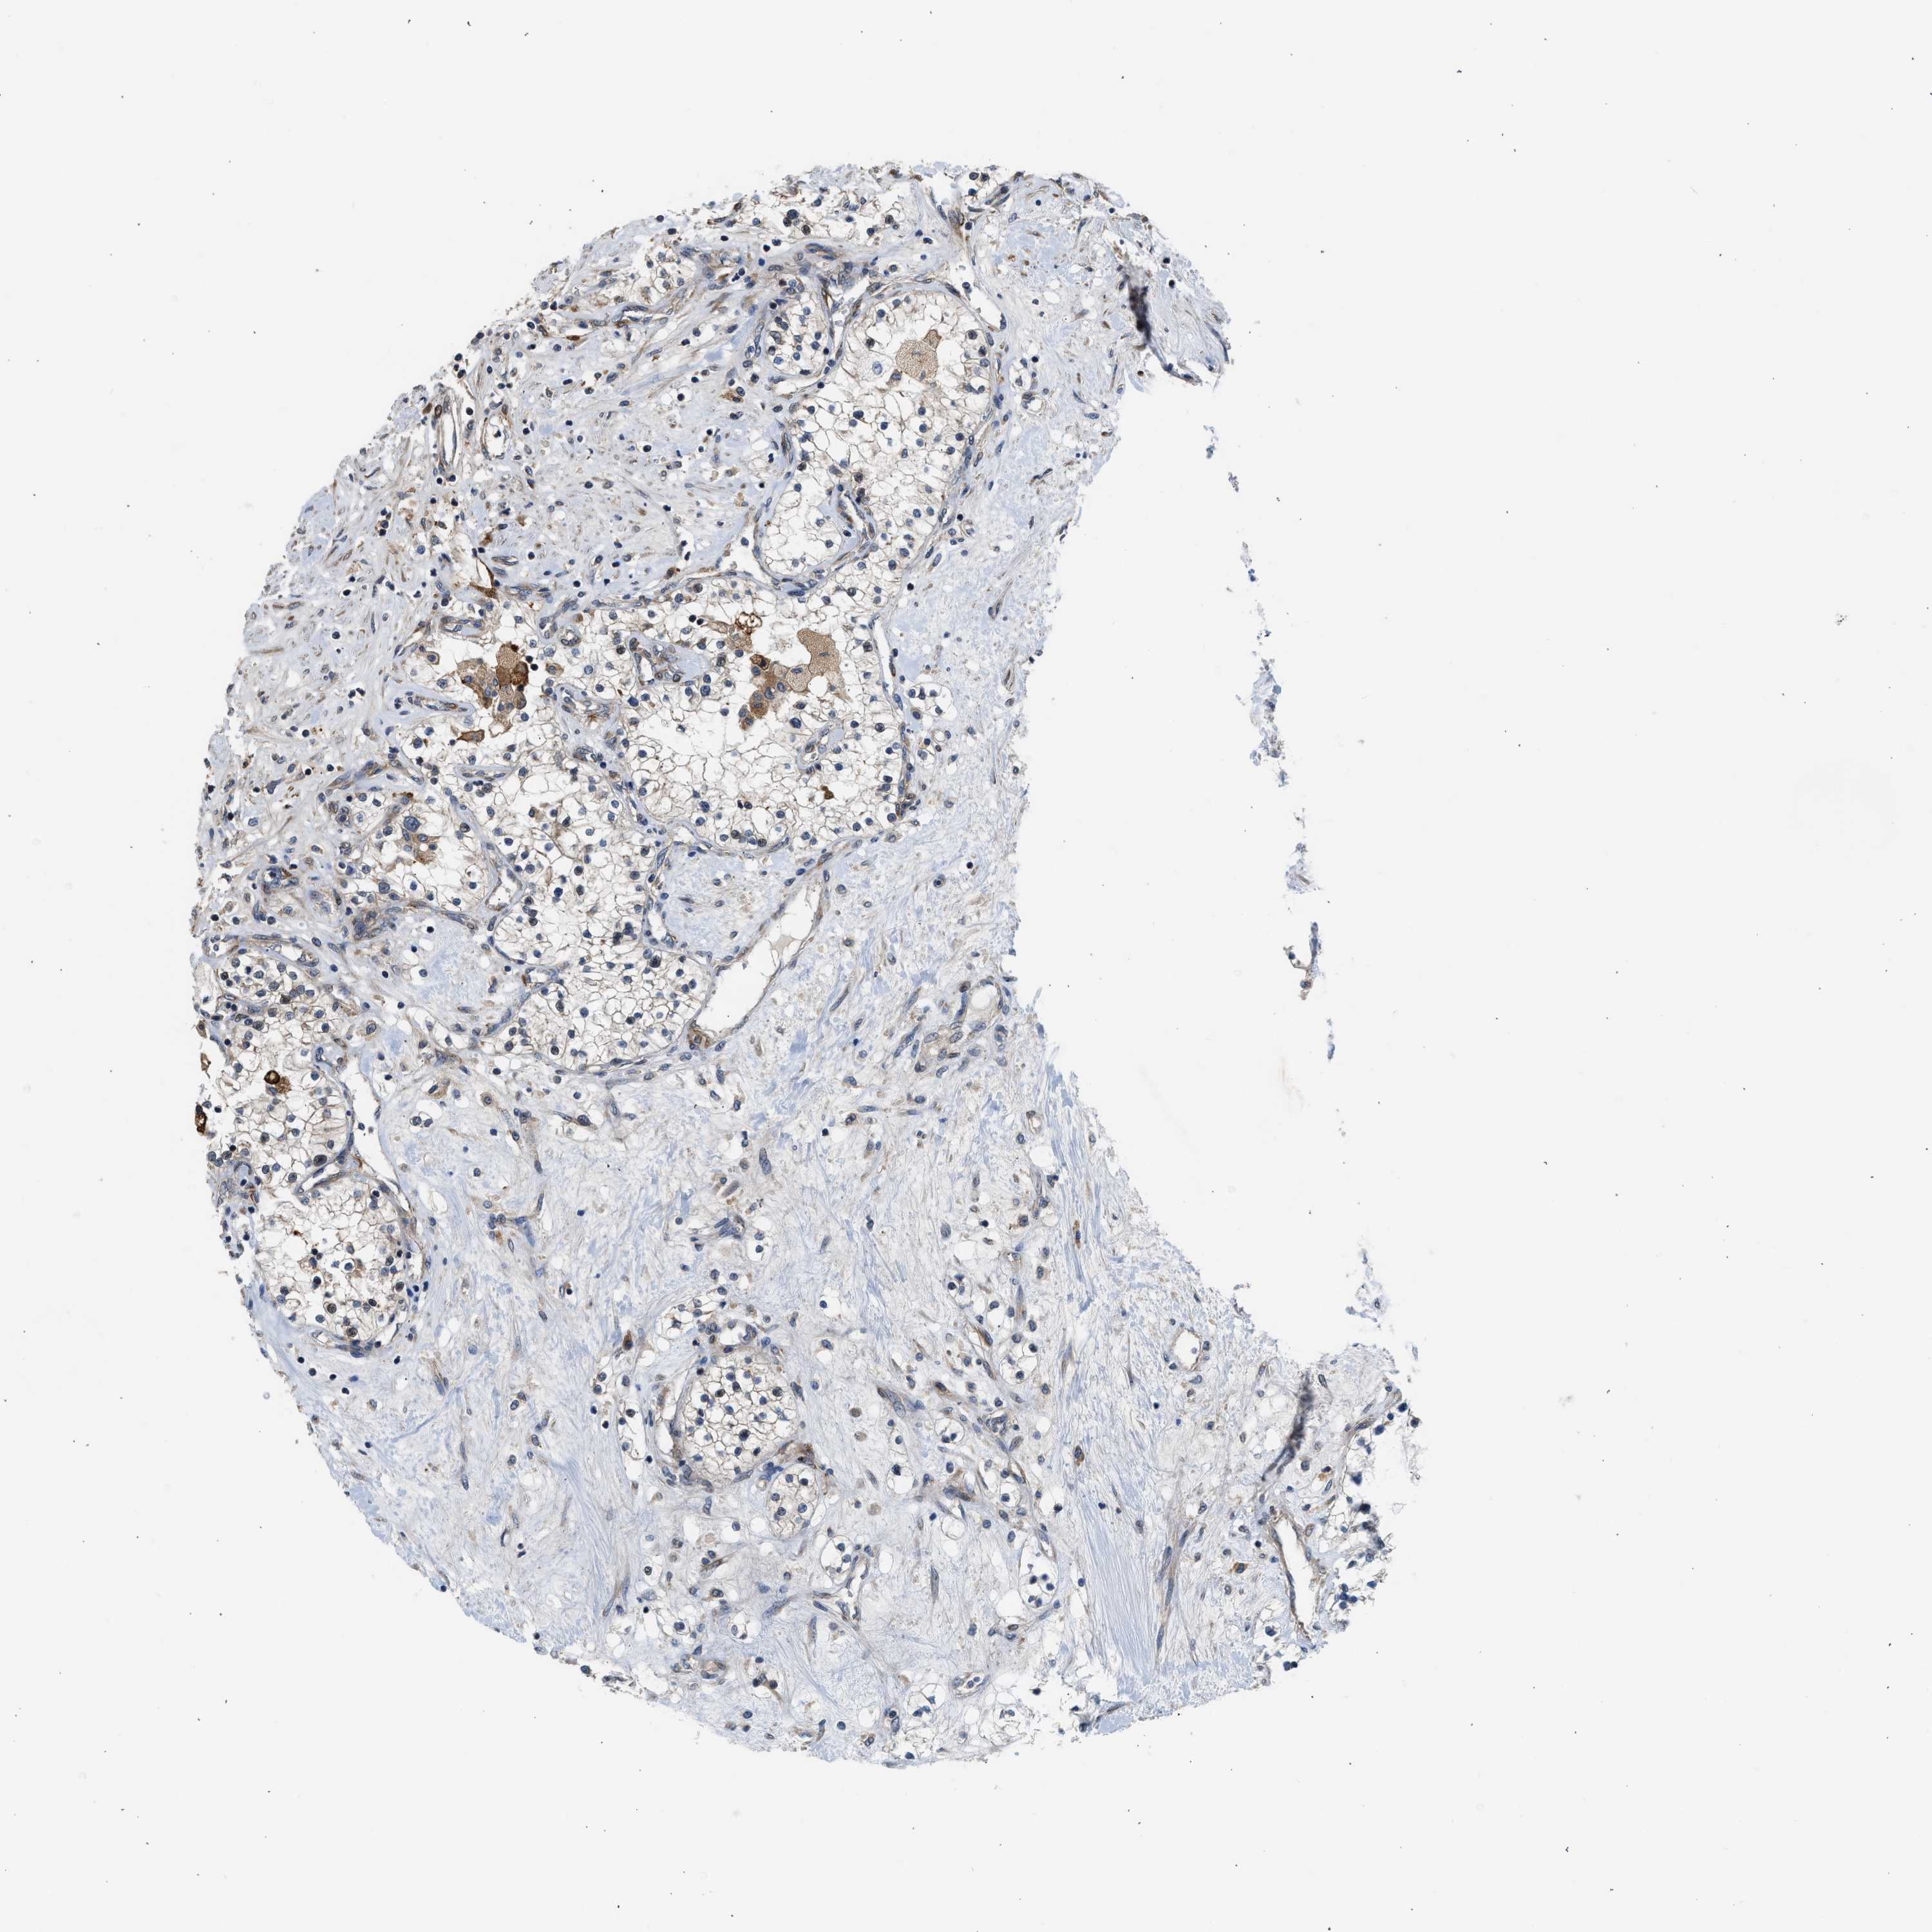

Renal cancer

Kidney chromophobe